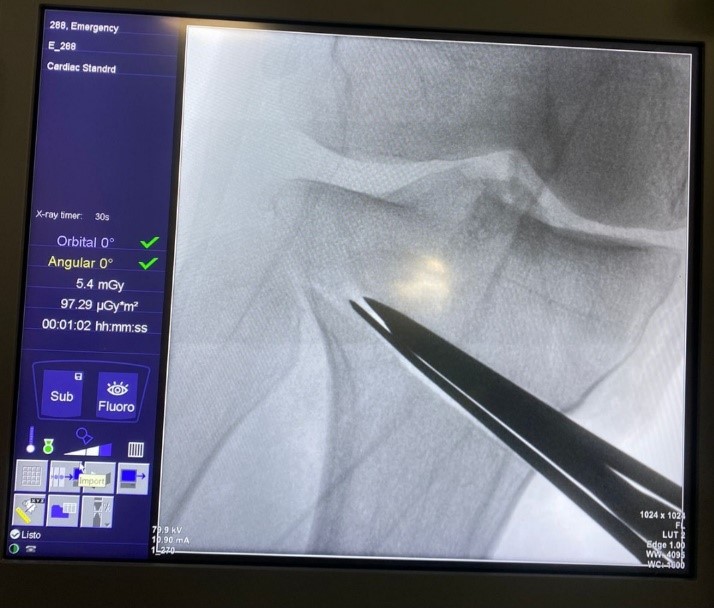

Mediante una incisión oblicua en cara anteromedial de la pierna se expuso la cara medial del tercio proximal de la tibia y liberación del ligamento colateral medial. Posteriormente, bajo visión directa con el intensificador de imágenes, se colocó una clavija desde medial, con dirección al tercio superior de la articulación tibioperonea proximal para marcar la localización del corte de la osteotomía (Fig. 2). Se realizó luego una osteotomía incompleta, que en el plano sagital debe ser paralela al slope tibial y sin afectar la cortical lateral de la tibia. Se inició el corte con sierra oscilante y se finalizó mediante escoplos. Luego de esta última, se procedió a su apertura gradual (Fig. 3). Una vez lograda la corrección planificada, se colocó una placa tipo Puddu, con los dos tornillos proximales para esponjosa, de 6.5 mm de diámetro y dos tornillos distales bloqueados, de 4.5 mm de diámetro (todas las placas fueron fabricadas en Argentina). Fijada adecuadamente la osteotomía, se rellenó la brecha de apertura con injerto óseo autólogo o alógeno liofilizado, mezclado con 1 g de vancomicina en polvo (Fig. 4). La colocación de la placa lo más cercana a la cortical posterior de la tibia tiene por objetivo tratar de evitar el incremento del slope tibial (Fig. 5).

Figura 2.Colocación de clavija medial y corte paralelo con sierra